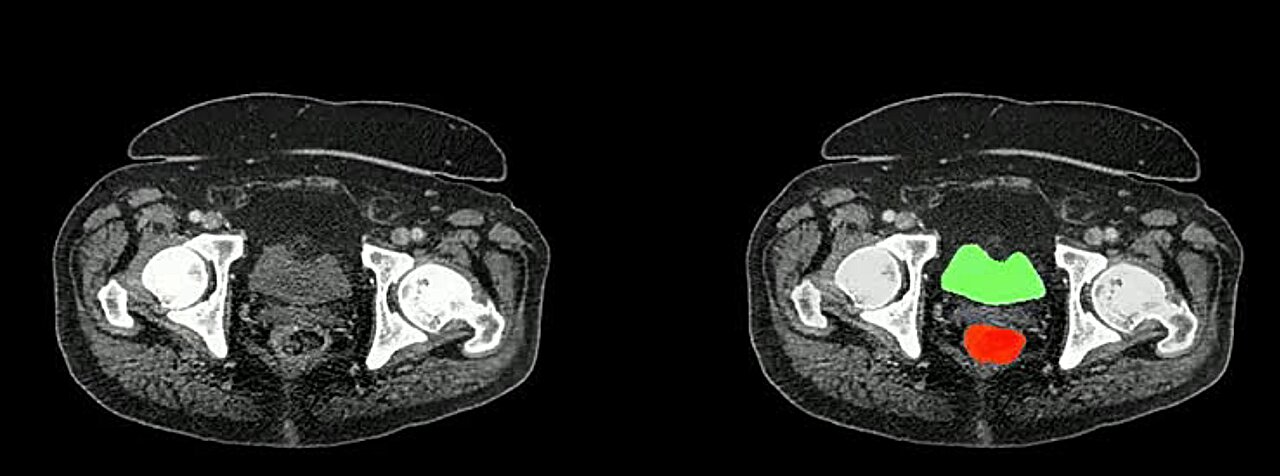

El método desarrollado combina tres modelos de IA entrenados en conjuntos de datos públicos de escaneos abdominales etiquetados para predecir anotaciones para conjuntos de datos no etiquetados.

Utilizando mapas de atención codificados por colores para resaltar áreas que necesitan refinamiento, el método identifica las secciones más críticas de las predicciones de los modelos para su revisión manual por parte de los radiólogos.